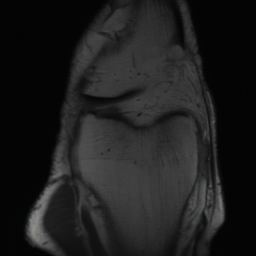

5.3 Out-of-Domain Generalisation

One way to test the generalization capability of the trained X-Diffusion is to test it on a completely different domain from an MRI dataset not seen during training. We report the single-slice results on NYU fastMRI [37, 82], a knee MRI dataset, using the X-Diffusion trained on the BRATS brain MRIs. The results are shown in Figure 9 and Table 2. It shows how successfully X-Diffusion is able to generate knee MRIs from a single image, despite not seeing knees at all in training. To qualitatively assess how realistic our generated 3D volumes were (produced from a single slice), we gave 20 generated examples alongside their real MRI counterparts to an expert orthopaedic surgeon. He was then asked to identify the real example from a given pair. The surgeon identified with certainty only 10 real knee MRIs out of 17, while could not decide on the remaining 3 of the 20 MRI pairs. This further validates the generated out-of-domain MRIs.